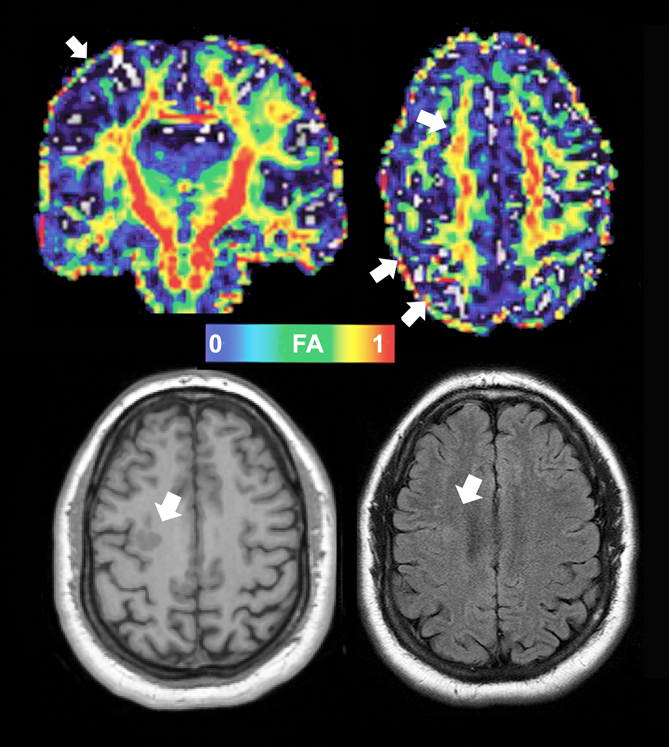

Engineer Team : RESONANCIA MAGNETICA Magnetic Resonance Imaging – Clinical Images Hallazgos por resonancia magnética cerebral de nuestro paciente. M, 21 … Imágenes por resonancia magnética anormales como predictoras de mal … Imágenes por resonancia magnética anormales como predictoras de mal … Lesiones en resonancia magnética (RM) del encéfalo y la médula espinal … Pin en Resonancia Magnética del Encéfalo A) Resonancia magnética cerebral (RMC) mostrando infartos en … Caso 1: Edema cerebral visualizado mediante RM. (A) Secuencia T1 plano … Rascacielos dormir pasta tac y resonancia diferencias retrasar … Pin on Apuntes de Enfermería y T.C.A.E Resonancia magnética cerebral secuencia T2, que muestra lesión … Meningitis aguda en la enfermedad de Behçet | Reumatología Clínica Resonancia magnética coronal normal del cerebro Fotografía de stock – Alamy Imágenes de resonancia magnética, la imagen de la cabeza en diferentes … Resonancia magnética cerebral A) protocolo T1 sagital (Caso 1). Se … Resonancia magnética cerebral. Secuencia T1 corte sagital. Atrofia … Resonancia magnética de cerebro, cortes axiales, secuencias T2. Señal … Resonancia magnética de cráneo. A y B) Cortes axiales FLAIR … Resonancia magnética (RM) de cerebro, corte axial ponderado en T2: la … RM cerebral: Interpretación paso a paso | Kenhub Resonancia magnética de cerebro, cortes axiales, secuencias T2. Señal … De Resonancia Magnética De Cerebro Foto de archivo – Imagen de arteria … Top 107+ Imagenes de resonancia cerebral normal – Destinomexico.mx -Imagen por resonancia magnética del cerebro. a) Cortes sagital y axial … resonanCia magnétiCa Cerebral donde se observa hiperintensidad a nivel … MRI (Imagen de resonancia magnética) – Tomografía computarizada de la … Meningioma – NCI Imágenes por resonancia magnética coloreadas del cerebro sano del … Resonancia magnética cerebral en secuencia FLAIR, que muestra lesiones … Contraste resonancia magnetica cerebral – senturinthegreen Relación de los espacios de Virchow-Robin con la enfermedad de … Gliomatosis cerebral – Instituto Nacional del Cáncer Pin en Neurology. Recomendaciones para la utilización e interpretación de los estudios de … Fotografía De La Proyección De Imagen De Resonancia Magnética Del … atmósfera Dirigir Cumplir anatomia resonancia magnetica Desarrollar … Pin en #MEDICINA,#SALUD Resonancia magnética de la nasofaringe De Resonancia Magnética De Cerebro Foto de archivo – Imagen de polilla … Atrofia cortical global de predominio parietal en la Resonancia … Resonancia magnética cerebral | Download Scientific Diagram Neuroblog: Resonancia magnética cerebral en la trombosis crónica de … De Resonancia Magnética De Cerebro Imagen de archivo – Imagen de … ¿Cuáles son los riesgos de la resonancia magnética? – Integra Salud … Resonancia magnética cerebral al decimocuarto día de ingreso: área … Resonancia magnética. Corte axial mostrando área infartada en el … Resonancia magnética cerebral del paciente AV evidenciando lesiones en … -Ressonância magnética de encéfalo mostrando múltiplas imagens … Resonancia magnética cerebral secuencia FLAIR (Fluid Attenuated … Resonancia magnética cerebral con protocolo de epilepsia, en sección … Resonancia magnética cerebral en corte sagital. Se observa una evidente … Resonancia magnética craneal en la que se evidencian lesiones … Logran visualizar el cerebro a detalle más completo tras una resonancia … Así decide el cerebro la severidad de un castigo De Resonancia Magnética De Cerebro, Imagen de archivo – Imagen de … A) Resonancia magnética cerebral; Secuencia Tof: oclusión de arteria … Un estudio asocia la ansiedad con la aparición rápida del Alzheimer IMÁGENES DE 18 F-PR04.MZ PET FUSIONADA CON RESONANCIA MAGNÉTICA … Imágenes por resonancia magnética anormales como predictoras de mal … Tumores de la región pineal – Instituto Nacional del Cáncer Epilepsia: una historia de voces y fantasmas | Neurología Contribución de las imágenes de resonancia magnética por tensor de … Resonancia magnética secuencia T2 plano coronal de quiste epidermoide … Resonancia Magnética Cerebral del paciente: a. Aumento de… | Download … Resonancia magnética cerebral 2022 Síndrome de hemiconvulsión-hemiplejía-epilepsia. Seguimiento de un caso … Enfoque Radiologico: La resonancia magnética permite detectar lesiones … Resonancia magnética craneal T1 con contraste que muestra angiomatosis … guidewiz – Blog Resonancia magnética cerebral, secuencia SWI. Ribete hipointenso en la … resonAnCiA mAgnétiCA de ColumnA Con gAdolinio. Corte sAgitAl en t1 de … SEMANA 12: FUNDAMENTOS DE RESONANCIA MAGNÉTICA NUCLEAR. INDICACIONES Y … DIAGNÓSTICO DE ESCLEROSIS MÚLTIP Magnetic resonance imaging of the brain – Alchetron, the free social … Resonancia magnética de órbitas | Instituto Radiológico Dr. E Castillo Alteración de la marcha en un paciente post-trasplante hepático Resonancia magnética cerebral de un paciente sano (Ay B) y paciente que … Utilidad de la resonancia magnética craneal para el diagnóstico de la … Resonancia Magnética Del Cerebro El Tumor Cerebral Foto de stock y más … De Resonancia Magnética De Cerebro Imagen de archivo – Imagen de … ABDALLA RADIOLOGIA: NEURINOMA ACUSTICO Atrofia cortical global de predominio parietal en la Resonancia … Resonancia Magnética : Producción de la imagen MRI Brain Scan — Stock Photo © Bunyos30 #18724051 Mri (imagen de resonancia magnética) Monitor con imagen de captura de … Tomografía computarizada vs resonancia magnética: diferencia y … Tumores Cerebrales – Unidad de Neurocirugía RGS Resonancia magnética de la columna, sección sagital. Observe los discos … La resonancia magnética, una técnica imprescindible en el diagnóstico … Perfusión Cerebral por Resonancia Magnética | ¿Qué es? ¿Necesita Contraste? Resonancia Magnética Cerebro A: resonancia magnética, T2 coronal preoperatoria; se observa lesión en … Resonancia magnética cerebral — Foto de stock © Bunyos30 #27340623 La resonancia magnética se perfila como detector de mentiras | Futuro … Resonancia magnética cerebral en T1 con gadolinio, cortes axial (a … MRI brain : show brain tumor at right parietal lobe of cerebrum — Stock … NEUROIMÁGENES EN ENFERMEDAD DE PARKINSON: ROL DE LA RESONANCIA …